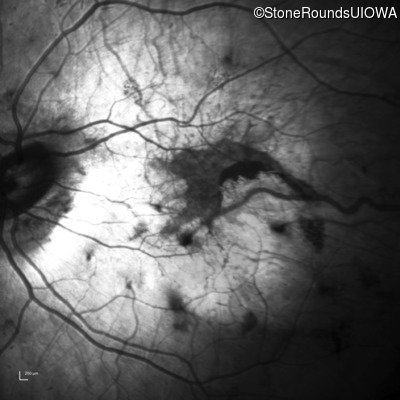

Infrared Fundus Photograph - Right - 5/350

Exemplar